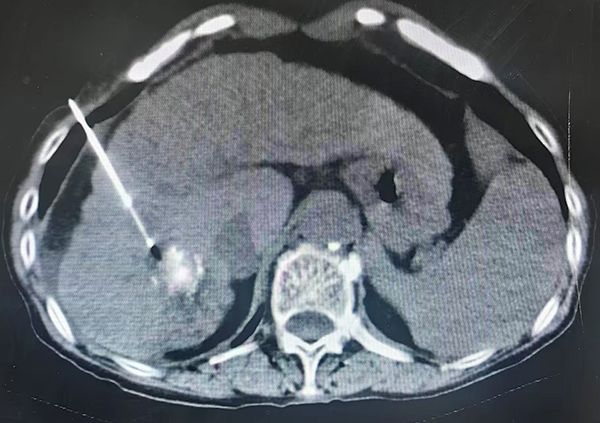

消融前CT

手术当日,介入医学科主任张应战主刀,团队凭借CT影像引导技术,将特制的消融探针精准穿刺至肿瘤内部。随后,利用氩气在针尖急速膨胀产生极低温(约-166℃),将肿瘤组织瞬间冻结成“冰球”,彻底摧毁癌细胞,再通过氦气复温,形成冷热循环,确保肿瘤细胞完全灭活。术中影像实时显示,消融范围完全覆盖病灶,边缘清晰,对周围正常组织影响极小。整个手术全程无痛、微创、精准、高效,患者耐受良好。